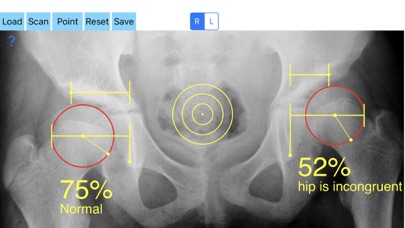

Treatment of incongruity is paramount importance because you have to address it early and the treatment of choice are usually corrective hip osteotomies. In order-from one hand to avert the natural course to the progression of secondary osteoarthritis (OA) and from another hand to avoid- in developing skeleton - to deteriorate more the hip dysplasia the congruity must be objectively and thoroughly evaluated especially at follow up of these procedures in both congruent and incongruent hips. Congruity between the femoral head and acetabulum is determined by the percentage of femoral head covered by the bony acetabulum. The congruity index (CI) is calculated (A/B- ratio converted to a percentage) by diving the (A) distance by the distance (B), where distance (A) is the distance between the teardrop to the lateral acetabular margin and (B) is the distance from the teardrop again to the lateral femoral head edge.

-Offers a very convenient way to determine the most accurate possibly way an objective value of congruity. By clicking three point at the x-ray picture on your iPhone screen and inserting the side the App calculates the congruity index (CI) which is the percentage of femoral head covered by the bony acetabulum. Congruity between the femoral head and acetabulum is expressed in percentage. Values of Coverage less than 75% is considered pathologic in another words the hip is incongruent